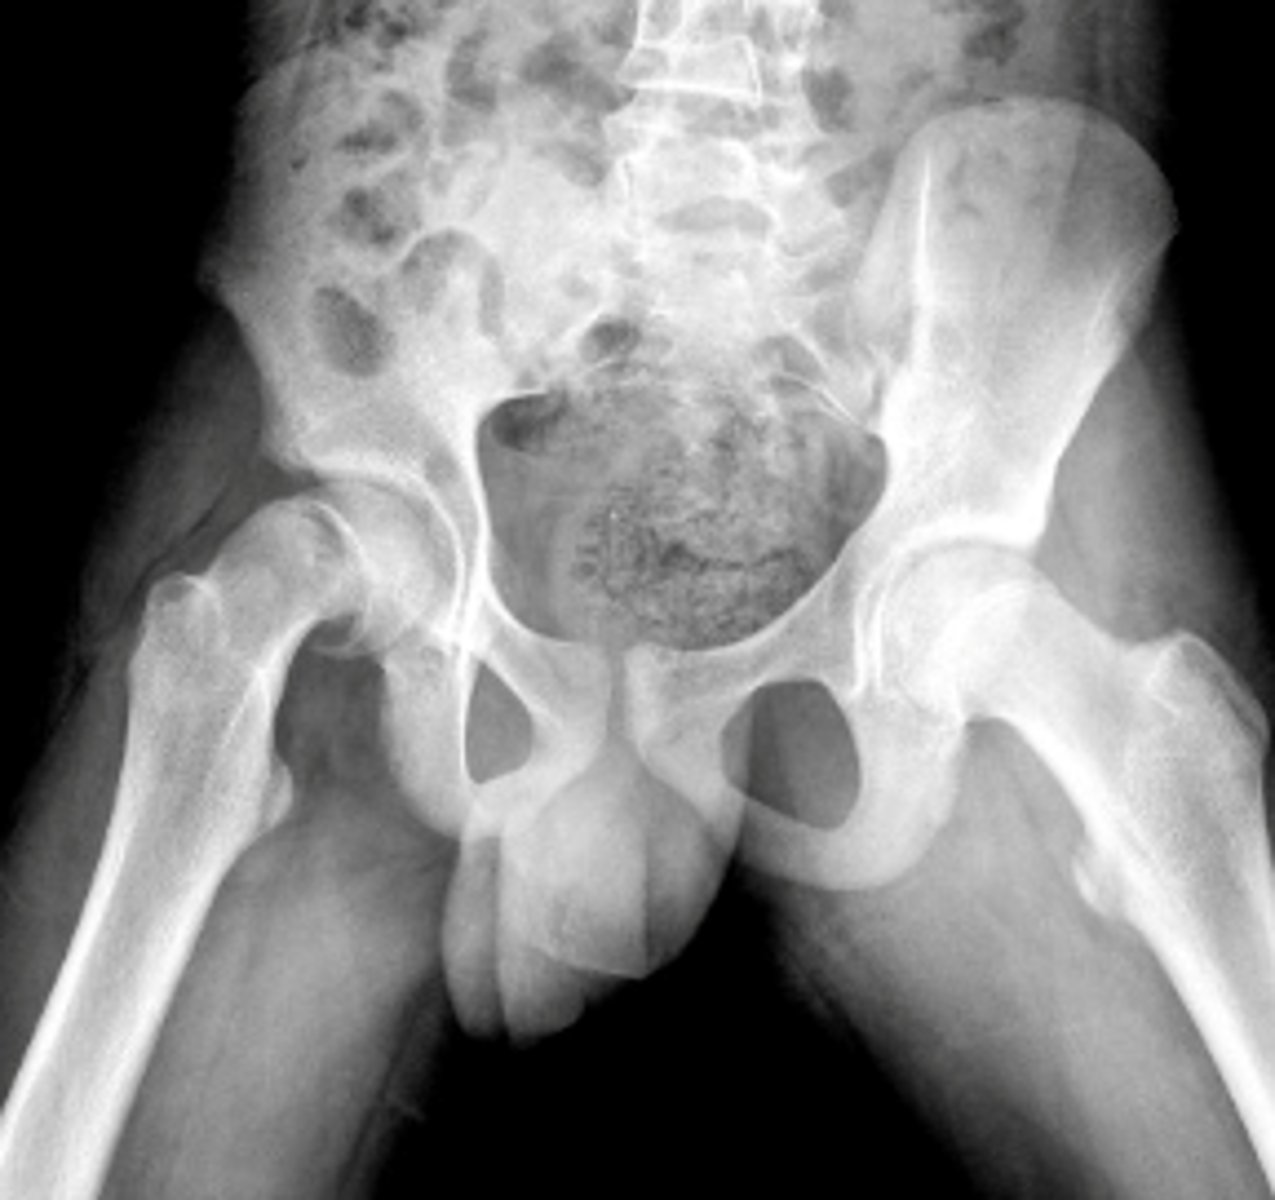

Legg-Calve-Perthes Disease

a type of osteochondrosis or disease of the growth centers in children which begins as a degeneration followed by regeneration and recalcification

*unknown etiology

**more likely in males, onset is generally 5-7 yrs of age (3-13)

FUNCTIONAL DEFICITS--> pain, limited ROM, gait changes

COMPENSATORY MOVEMENTS--> limit motion/use of the joint, limit overall activity level

COURSE--> bone necrosis, revascularization, reossification over a period of 24-36 months